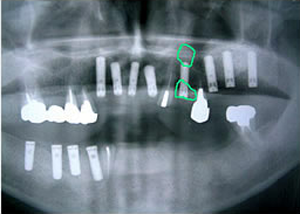

7.下の前歯部に4本

インプラント埋入

8.この部は薄い骨があっただけでインプラントの先端1/3を骨に埋入。あとはすべて骨を作ってあります。

上にのせた膜の中にチタンのフレームがわずかに映っています。